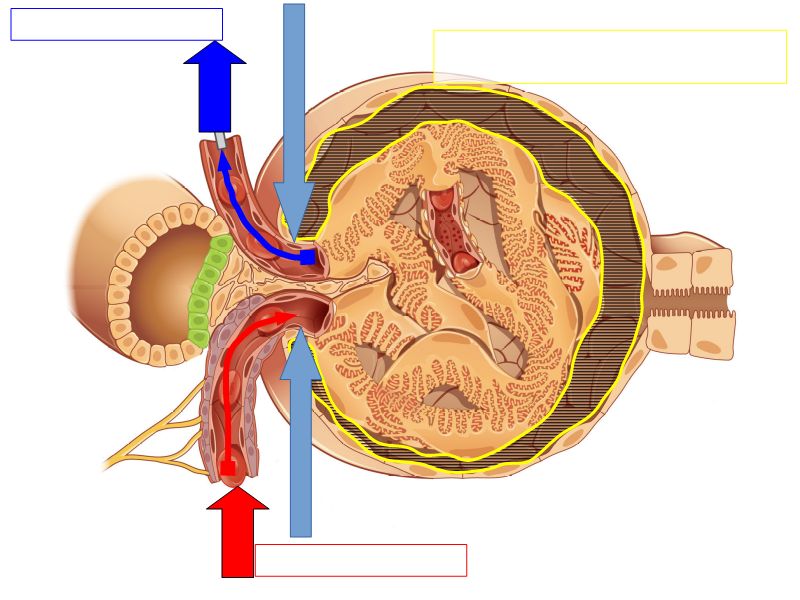

Blood flow

- Efferent arteriole

- Smooth muscle in media

- Capillaries

- Fenestrated

- Afferent arteriole

- Smooth muscle in media